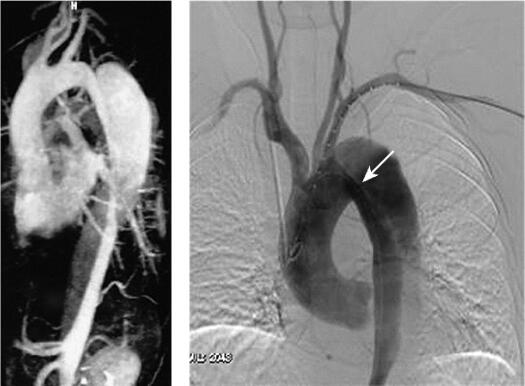

MRI:MR true FISP序列,清楚显示真假腔、内膜破口,并在电影中观察到血流在真假腔中运动。MRA表现为降主动脉呈“双腔”主动脉,真腔受压变窄,假腔较大,假腔自降主动脉延续至腹主动脉;头臂血管分支均起自真腔,腹腔干及肠系膜上动脉均起自真腔。

图1 主动脉夹层

DSA:降主动脉呈“双腔”主动脉影,真腔较小,位于前方,假腔较大,位于后方,内膜破口位于左锁骨下动脉以远的主动脉峡部,在真假腔之间的线状负影为内膜片。头臂血管均起自真腔。